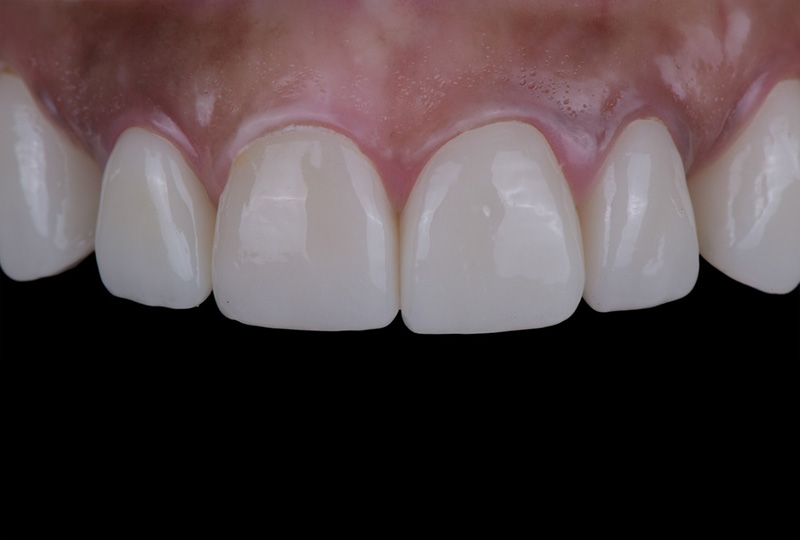

• 治療前

• 治療後

症例名 被せ物の下が虫歯になり折れてしまい、抜歯適応になってしまった歯をインプラントを抜歯と同時に埋入する事で、インプラントにより審美面機能面で回復を行った症例

主訴/ニーズ 被せ物が外れた。できれば元通りに直して欲しい。人前に立つ職業なので、見た目が自然なのが1番大事。

治療内容 この患者様は、被せ物が取れてしまったため再装着を希望されて来院されました。 しかし、診査の結果、被せ物の土台となる歯根が折れており、残念ながら抜歯以外の選択肢がない状態でした。見た目や機能、そして長期的な安定性を考慮したうえで、今回は抜歯と同時にインプラントを埋入する「抜歯即時インプラント」を行いました。 この方法を選択することで、治療期間を大幅に短縮できるだけでなく、周囲の歯ぐきの退縮を最小限に抑え、より自然で美しい仕上がりが期待できます。 抜歯即時インプラントは、すべてのケースで行えるわけではなく、適応症の見極めが非常に重要です。この患者様の場合、骨の状態や感染の有無などを慎重に確認したうえで、適応可能と判断し実施しました。結果として、見た目・機能ともに良好な経過を得ることができました。患者様も結果に非常に満足されました。

費用 60万円